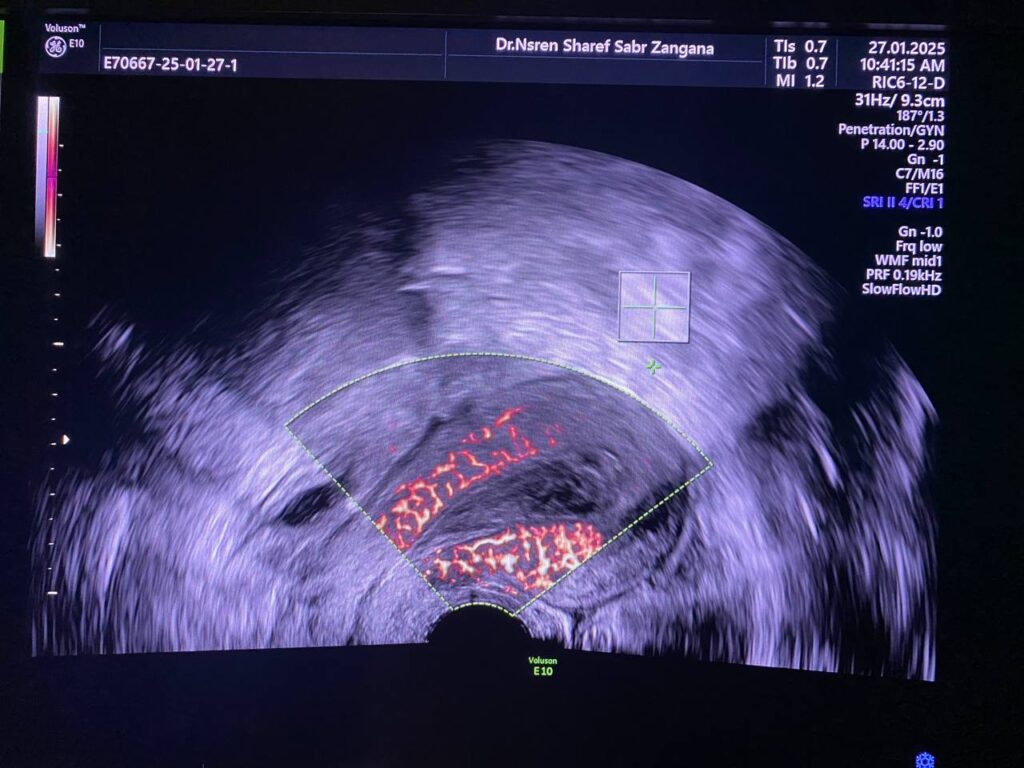

Heterogenous avascular endometrial thickening ( blood clot?) with Presence of hypoechoic vascular (score 4 ) mass within the distal part of the cervix (at level of external os), it’s size 15x15mm , its arise ( single pedicle vascular ) from upper cervical canal nearly (at level of internal os) , mostly pedunculated submucosal fibroid ? polyp? other cervical mass